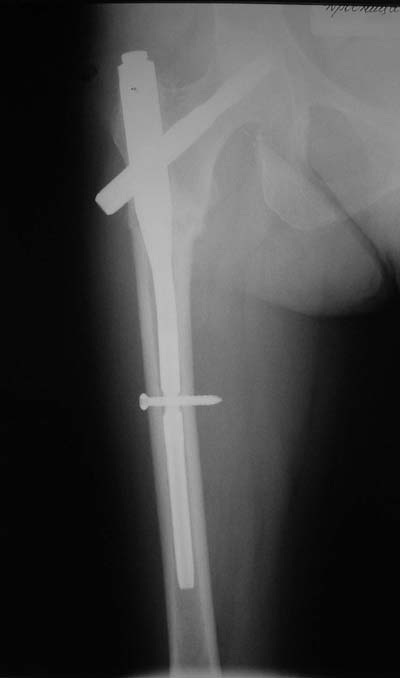

Не думаю так. см вложение.

Ну, после помещения туда такого гвоздя даже без дистального винта заметной нестабильности уже не остается ;-)

Для такого перелома вполне может быть использован диафизарный штифт, который отечественного производства я даже боюсь считать во сколько раз дешевле... Недавно несколько примеров я закидывал.